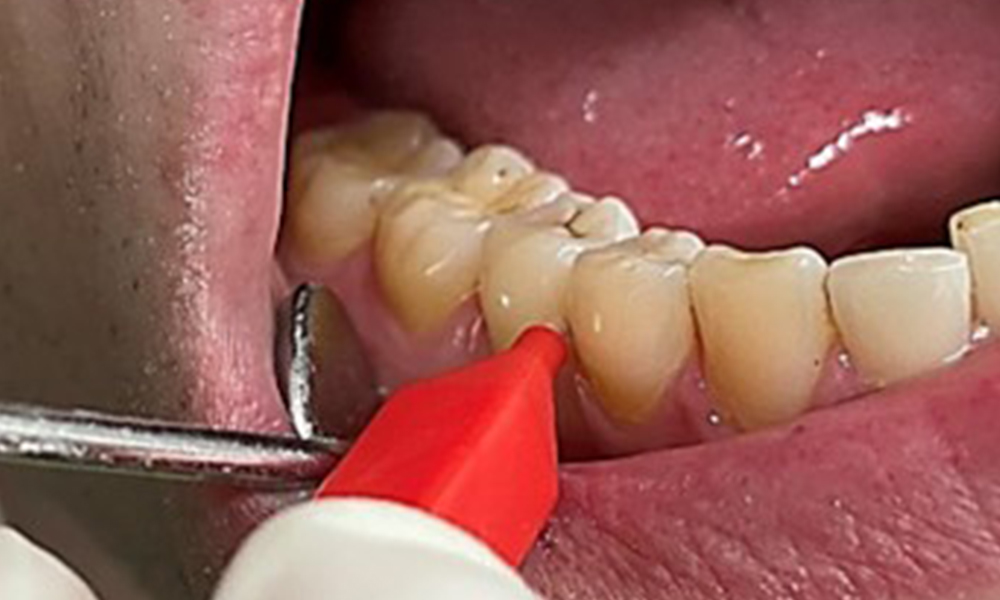

Discolouration caused by nicotine and tea consumption can be removed easily using an air polisher (Fig. 11).

Air polishing system use in the mandibular frontal lingual area (here, Proxeo Aura, W&H)

Fig. 11 Air polishing system use in the mandibular frontal lingual area (here, Proxeo Aura, W&H), © Dr R. Krapf

When using more abrasive powder, it is essential to work from a cervical to coronal direction and never point the outlet nozzle towards the gingiva to prevent potential emphysema. Good suction on the contralateral side is essential to reduce aerosol formation (Fig. 12).